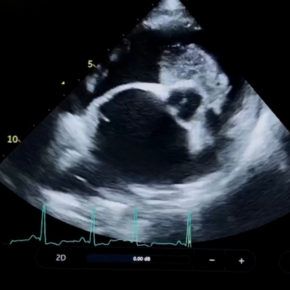

It has been of huge benefit to the mental health of our nation to have our pets alongside us at such a challenging time. Sadly this brought a new generation of puppies needing help with congenital heart defects. Fortunately, we have helped many families to keep their much-loved pets, performing life-saving interventional (keyhole) surgery for problems such as patent ductus arteriosus or severe pulmonic stenosis. This success reflects the diligence of our referral vets, detecting murmurs and helping owners and pets to get the best care despite the difficult circumstances.